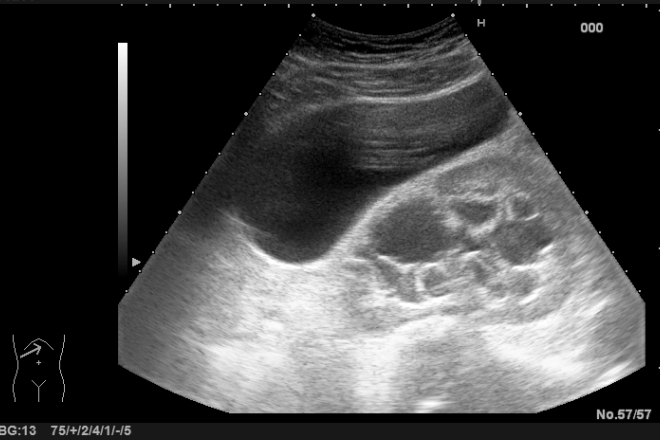

El ultrasonido hepático es una modalidad de ecografía que nos permite evaluar el hígado y detectar diversas enfermedades, como agrandamientos, infiltraciones grasas, hepatitis crónicas, cirrosis, quistes, tumores y lesiones traumáticas. Es imprescindible conocer las características distintivas de cada enfermedad; por ejemplo, un quiste hepático se visualiza en el ultrasonido como una estructura anecoica con una pared bien definida y reforzamiento acústico posterior debido a la continuidad con el hígado.

Además de la información proporcionada en los trabajos del módulo 2, se llevó a cabo una investigación sobre diversas patologías hepáticas y el papel del ultrasonido en su diagnóstico. Las patologías estudiadas incluyeron trauma hepático, cirrosis, hepatopatías crónicas, quiste hepático gigante y masas hepáticas sólidas. En todos estos casos, la ecografía hepática demostró ser de gran utilidad para diferenciar las diferentes estructuras hepáticas, convirtiéndose en un método valioso siempre y cuando se conozcan las características clínicas, epidemiológicas y morfológicas de las enfermedades en cuestión.